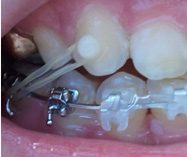

아!그리고 하악 밑에 달앗던 스크류 하나 뺐는데..정말..드라이버로 나사를 빼는..그런 기분이랄까

아프진 않았는데..기분이좀 이상했다는!!!

일단 한개만 뺐어요~~! 아 !그리고 제 옆모습 보면 정말 입이 엄청나게 들어갔어요~~